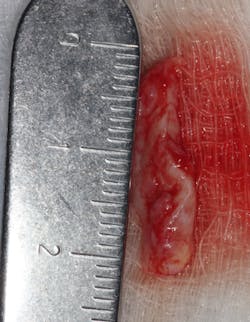

A split- to full-thickness intrasulcular incision was made on the facial of teeth Nos. 2 through 4. Upon completion of flap elevation, an intraosseous cyst associated with the distobuccal root of No. 3 was noted perforating the buccal plate and adherent to the overlying flap (figure 2). A sharp dissection separated the cyst from the flap (figure 3), and the cyst—measuring roughly 1.0 x 0.75 x 0.5 cm—was enucleated intact, leaving an intraosseous defect (figures 4a and 4b).

The pathology report identified the specimen as a 1.1 x 0.8 x 0.5 cm inflammatory cyst of the maxilla (figure 12). The patient now exhibits 10 mm of attached gingiva on the facial of tooth No. 3. The recession defect has been completely eliminated by a combination of the SECT graft and the full-coverage restoration (figure 13). The periapical radiograph shows no residual periapical pathology. After one year, the patient continues to be asymptomatic and is functioning well with the tooth.